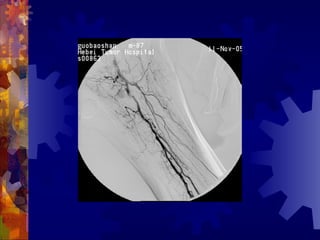

糖尿病足的检查

4. 足部 X- 线检查

5. 动脉造影(下肢)

6. 溃疡表面分泌物的培养

男, 86 岁

双下肢多普勒血流图未探及血管

动脉造影血管闭塞